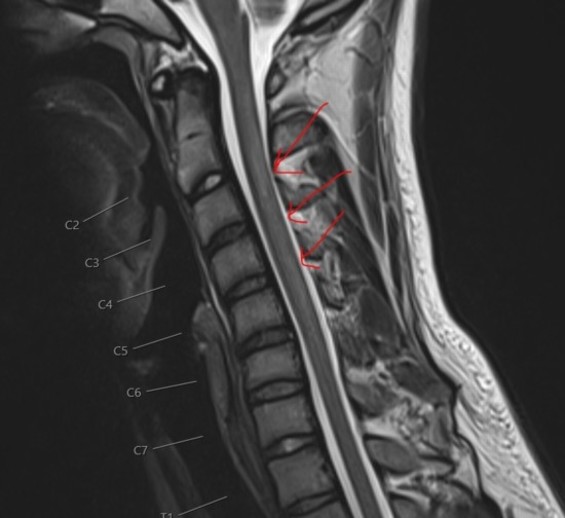

בתמונות: תהליכי ניוון במערכת העצבים המרכזית, לאחר שאיפת גז קצפות | צילום: הקריה הרפואית רמב"ם